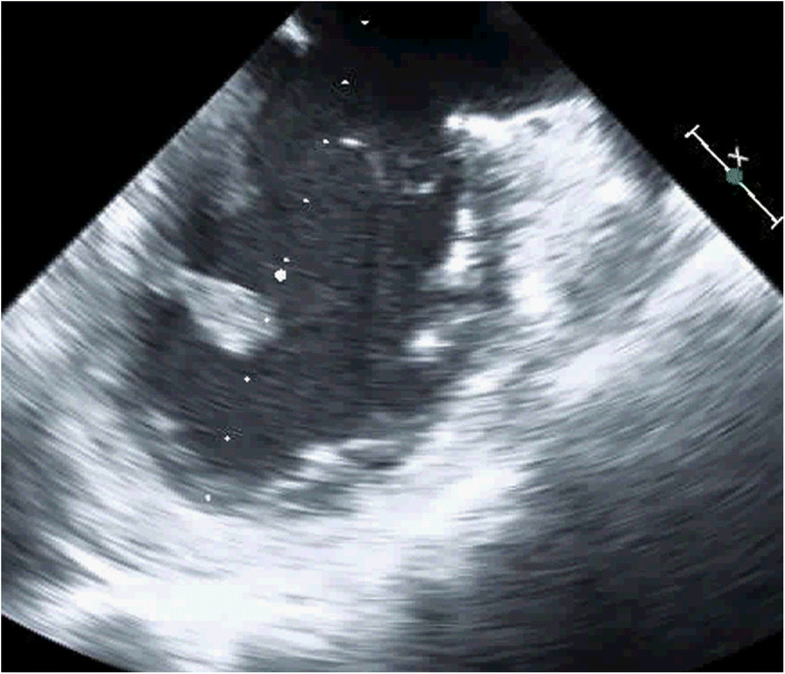

(PDF) Left Atrial Mural Endocarditis Diagnosis by Transesophageal

(PDF) Left Atrial Mural Endocarditis Diagnosis by Transesophageal What Is Mural Endocarditis Infective endocarditis (ie) is an infection involving the endocardial surface of the heart, including the valvular structures, the. It's most commonly caused by. Endocarditis is a term that refers to inflammation of the endocardium, the thin inner membrane that covers the heart and heart valves. It’s usually caused by a bacterial infection,. It may cause fever, heart murmurs, petechiae, anemia,. What Is Mural Endocarditis.

Figure 1 from Left Atrial Mural Endocarditis Diagnosed by What Is Mural Endocarditis Endocarditis is a term that refers to inflammation of the endocardium, the thin inner membrane that covers the heart and heart valves. Infective endocarditis is infection of the endocardium, usually with bacteria (commonly, streptococci or staphylococci) or fungi. Infective endocarditis (ie) is an infection involving the endocardial surface of the heart, including the valvular structures, the. Infective endocarditis is defined. What Is Mural Endocarditis.